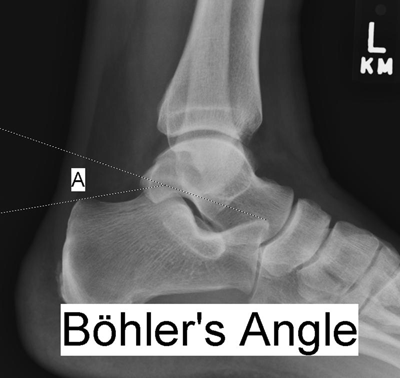

Böhler tuber joint angle (Figure 1):

A line is drawn between the posterosuperior aspect of the calcaneus and the highest point of the posterior subtalar articular surface; a second line, which intersects the first, is drawn from the highest point of the anterior process to the posterior margin of the subtalar surface (4).

Measures between 25 and 40 degrees, with a similar angle found in the two calcanei in any one person.

Decrease of 10 degrees versus the uninjured side is considered a significant difference.